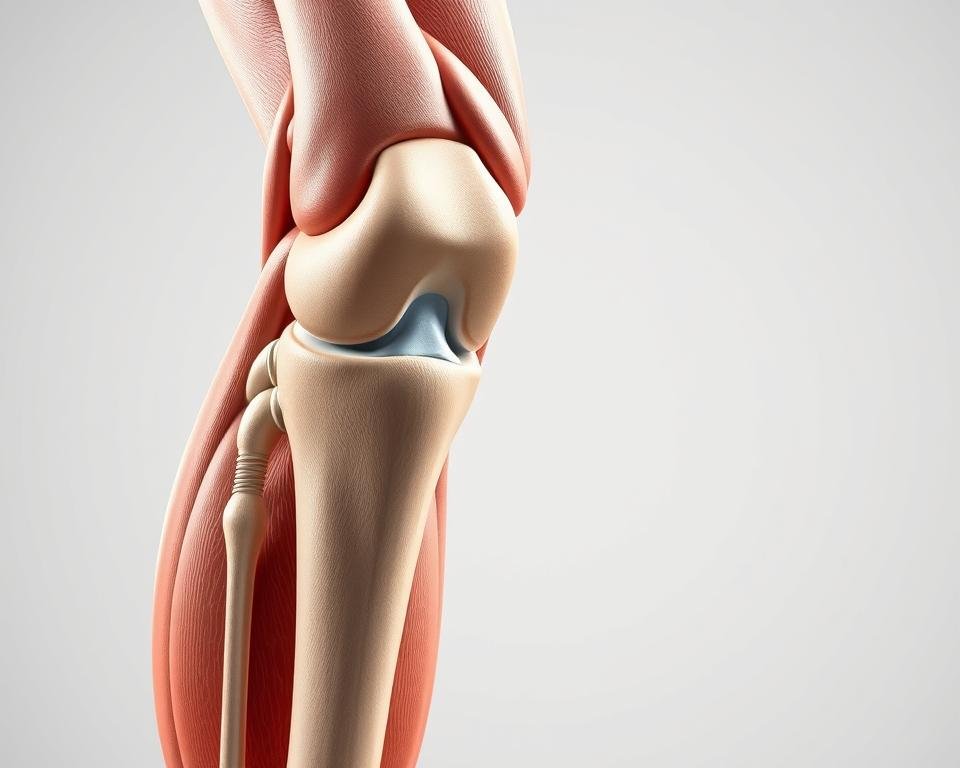

La articulación de la rodilla posee una estructura compleja: ligamentos, meniscos y cartílagos trabajan en conjunto. Cualquier alteración en estos componentes puede generar molestias persistentes. Por ejemplo, una rotura de menisco o tendinitis provocan dificultad para apoyar la pierna.

Anatomía de la Rodilla y Factores de Carga

La complejidad biomecánica de esta articulación explica su vulnerabilidad. Tres huesos convergen en su estructura: fémur, tibia y rótula. Su interacción precisa permite movimientos fluidos al caminar o flexionar.

Cuatro ligamentos principales garantizan estabilidad. Los cruzados controlan desplazamientos anteriores/posteriores, mientras los colaterales limitan movimientos laterales. Cualquier lesión en estas estructuras compromete la función articular.

El cartílago actúa como amortiguador natural. Recubre las superficies óseas reduciendo la fricción durante el movimiento. Junto a los meniscos, distribuye las cargas de impacto de forma eficiente.

Los músculos periarticulares (cuádriceps, isquiotibiales) actúan como soporte dinámico. Su fortalecimiento reduce hasta un 40% la presión sobre las rodillas, según estudios de biomecánica.